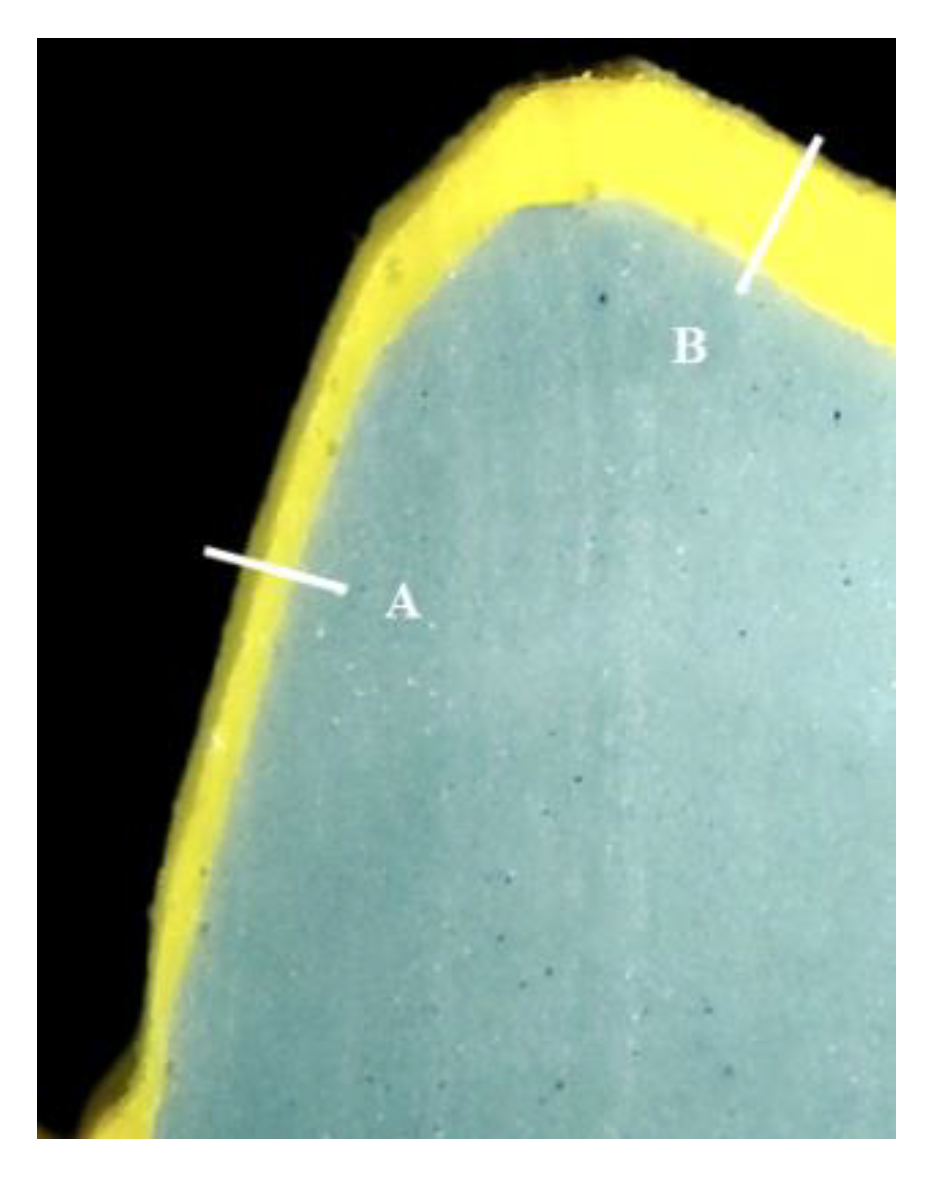

The internal fit was measured in all groups of specimens finished until the glazing stage of the porcelain firing procedures to compare the internal fit based on the different manufacturing techniques. The silicone replica technique, which is widely used in many studies and proven to be credible and accurate, was used to determine the internal space measurement [50,51]. The internal surface of each specimen was filled with polysiloxane silicone impression material (Honigum-Light, DMG, Hamburg, Germany) to determine the internal space. Each specimen filled with soft silicone material was mounted on the corresponding abutment models, which were then pressured in the direction of the tooth’s longitudinal axis. After the silicone was set, the specimens were removed, and a low-flowable polysiloxane silicone impression material (Honigum-Mono, DMG, Hamburg, Germany) was applied. After the final setting, the silicone was cut in a mesio–distal and linguo–buccal direction with a scalpel. The cross-section of the cut piece was observed at ×100 magnification using metallurgical microscopy (EGVM-452M, Easytech, An-yang, Republic of Korea), and the thickness of the silicone was measured to determine the internal gap (Figure 10). The internal gap of all specimens was measured in the mesio–distal and bucco–lingual part of the axial wall, cusp, and occlusal areas.

Figure 10.

Internal fit of PFM dental single restoration at ×100 magnification. A: axial internal fit, B: occlusal internal fit.